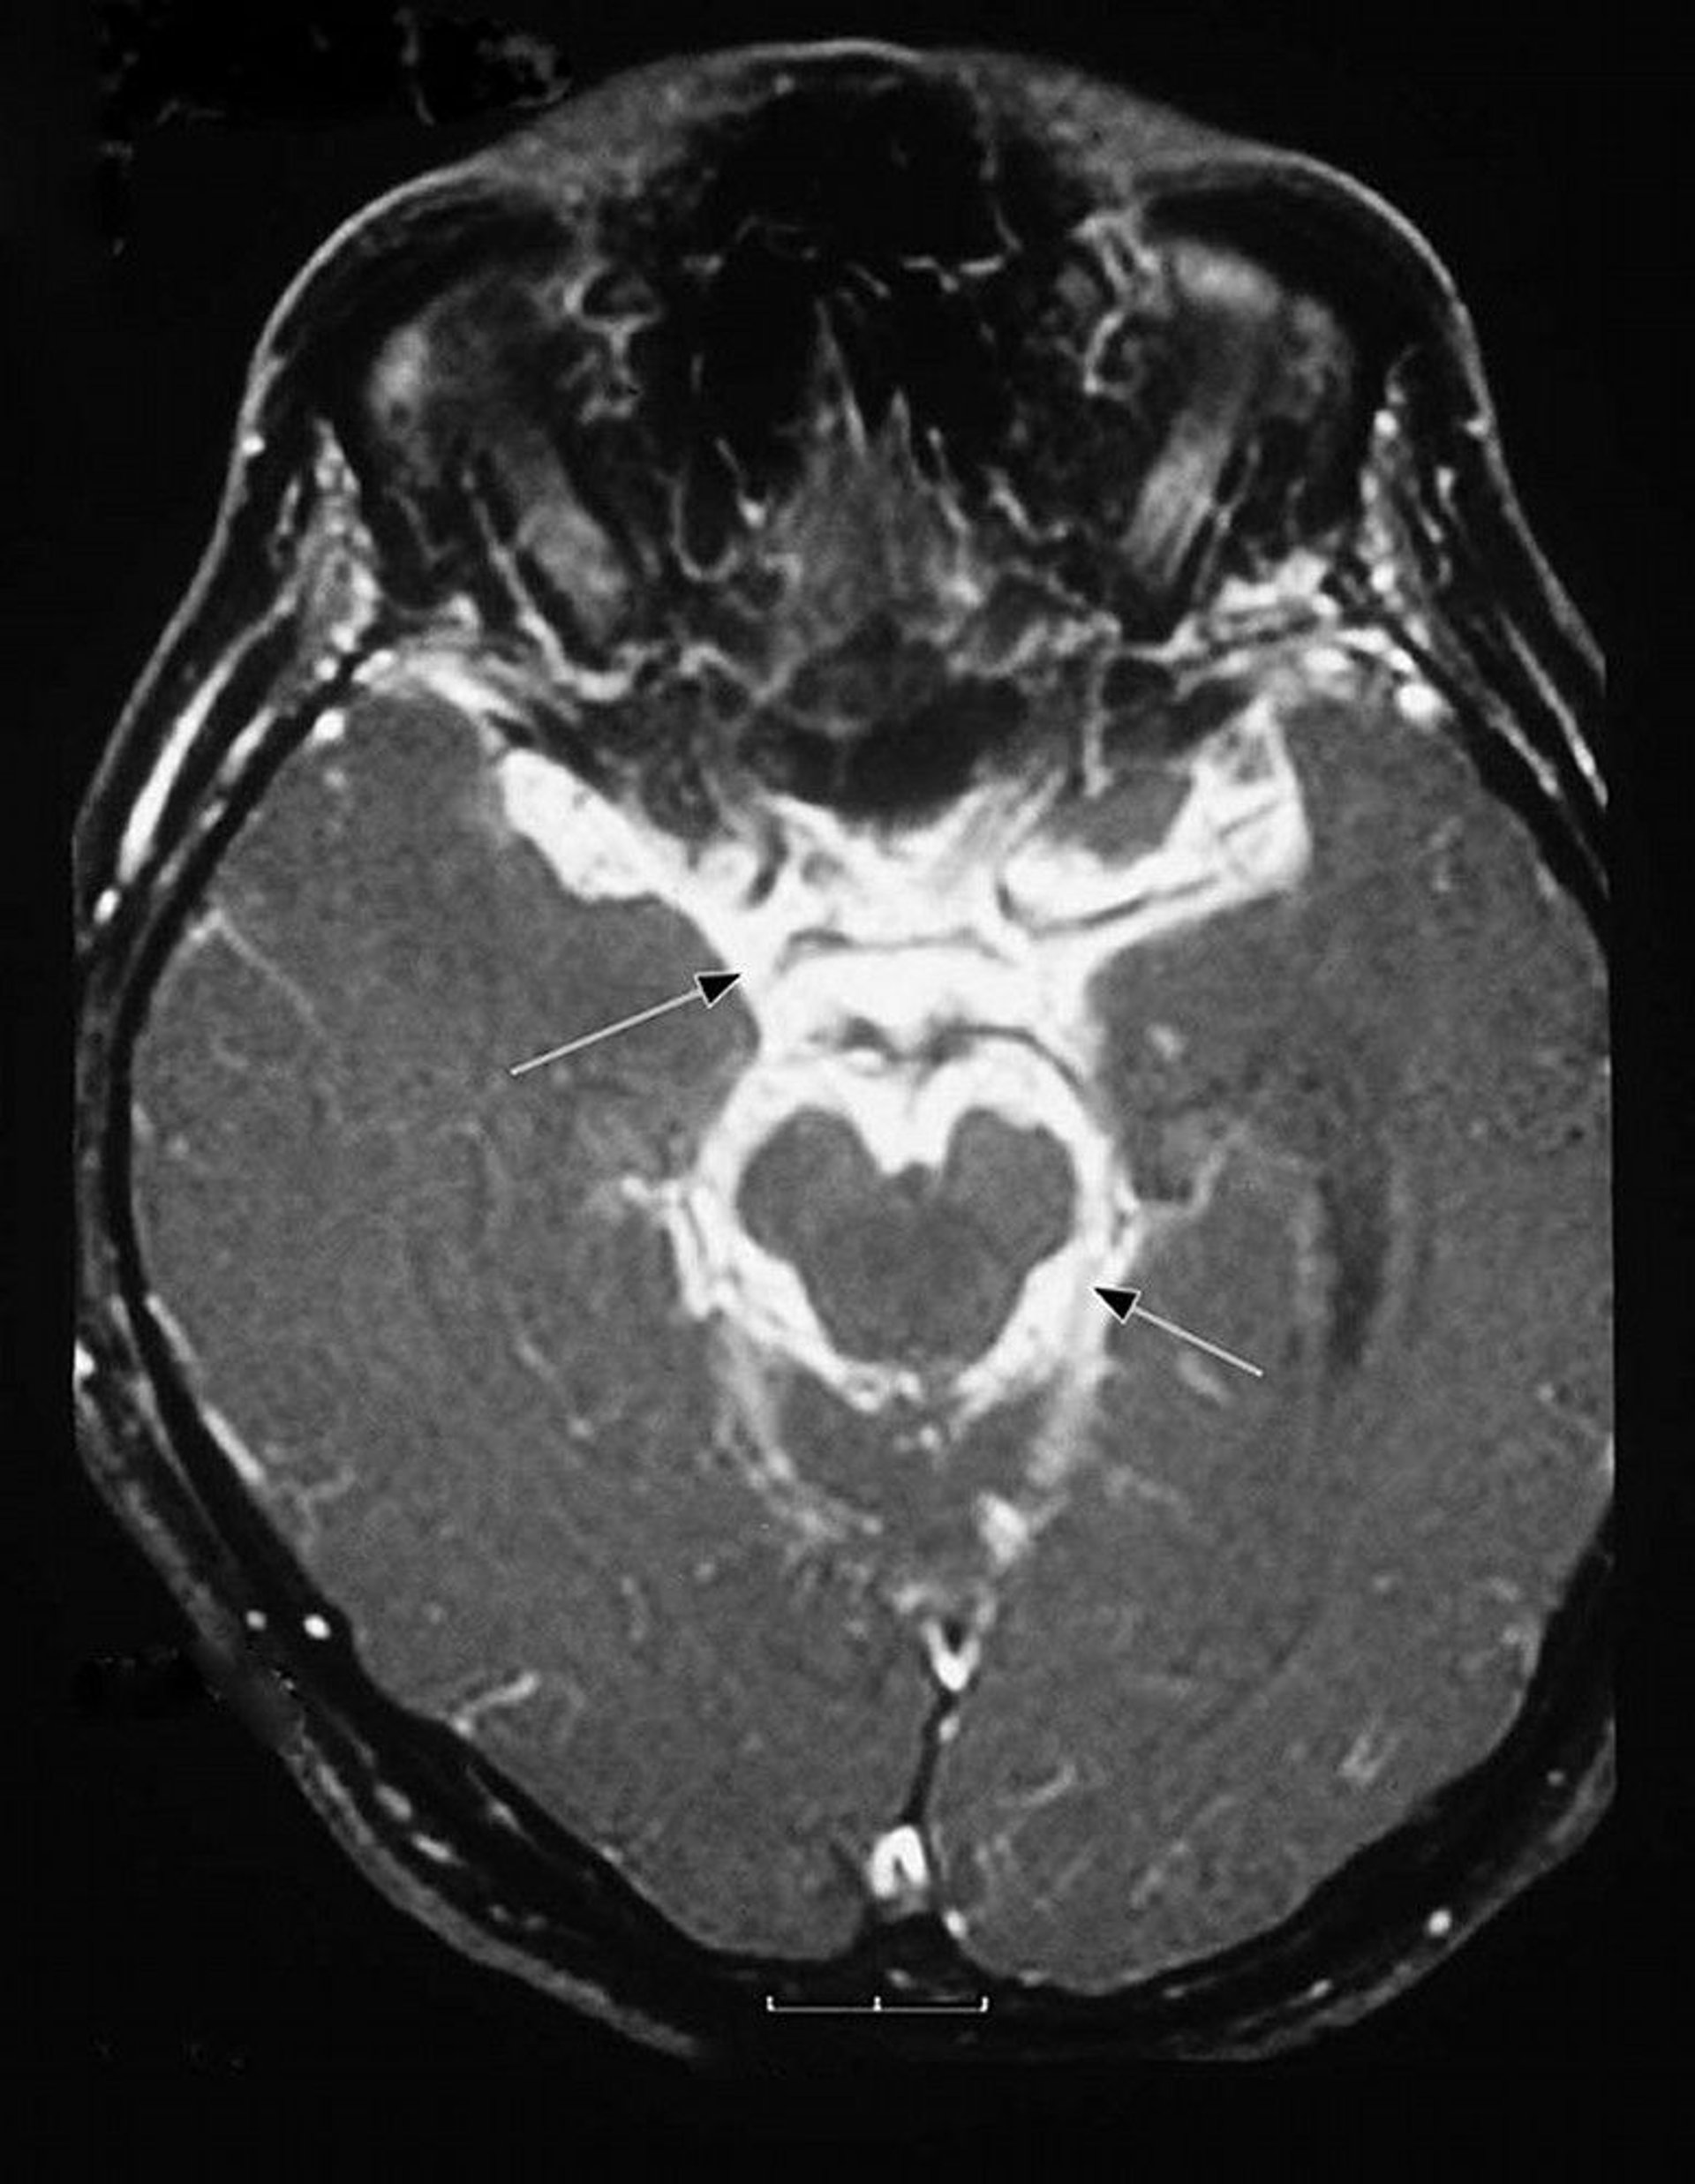

This magnetic resonance imaging (MRI) scan of a patient with tuberculous meningitis shows intense inflammatory exudate at the base of the brain (basilar meninges [arrows]) and surrounding the brain stem.

Image courtesy of John E. Greenlee, MD.